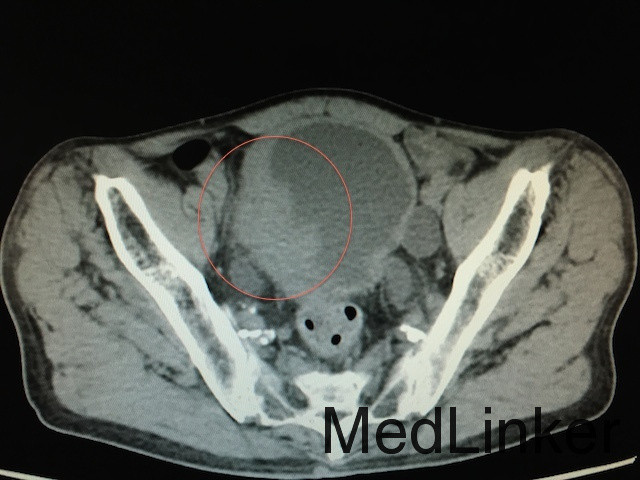

ct增强见膀胱左侧壁新生组织明显强化,符合肿瘤特征.

辅助检查:泌尿系ct(如下图所示):膀胱实性占位,增强扫描肿物呈不均匀

术前ct: 膀胱肿瘤▲术后:原位"w"形新膀胱▲ 腹腔镜下淋巴结清扫